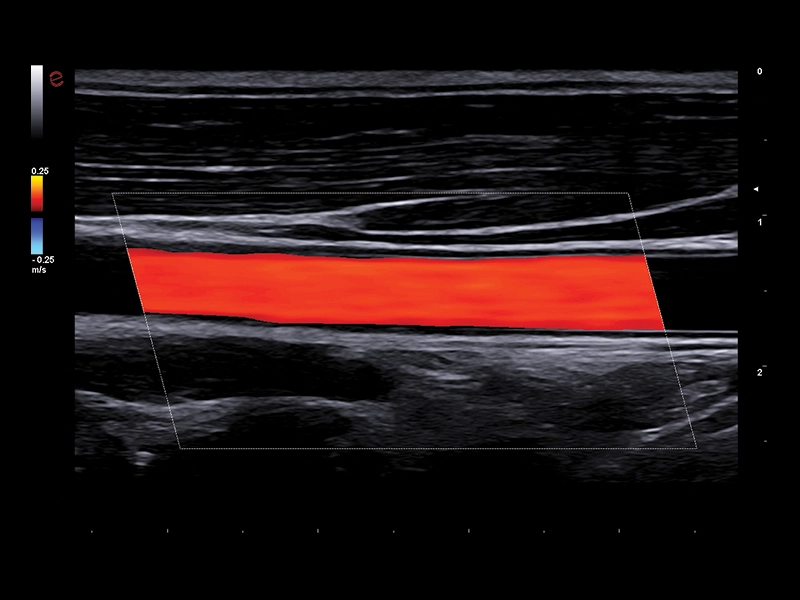

MyLab™Omega - Common Carotid Artery CFM

MyLab™Omega - Common Carotid Artery CFM